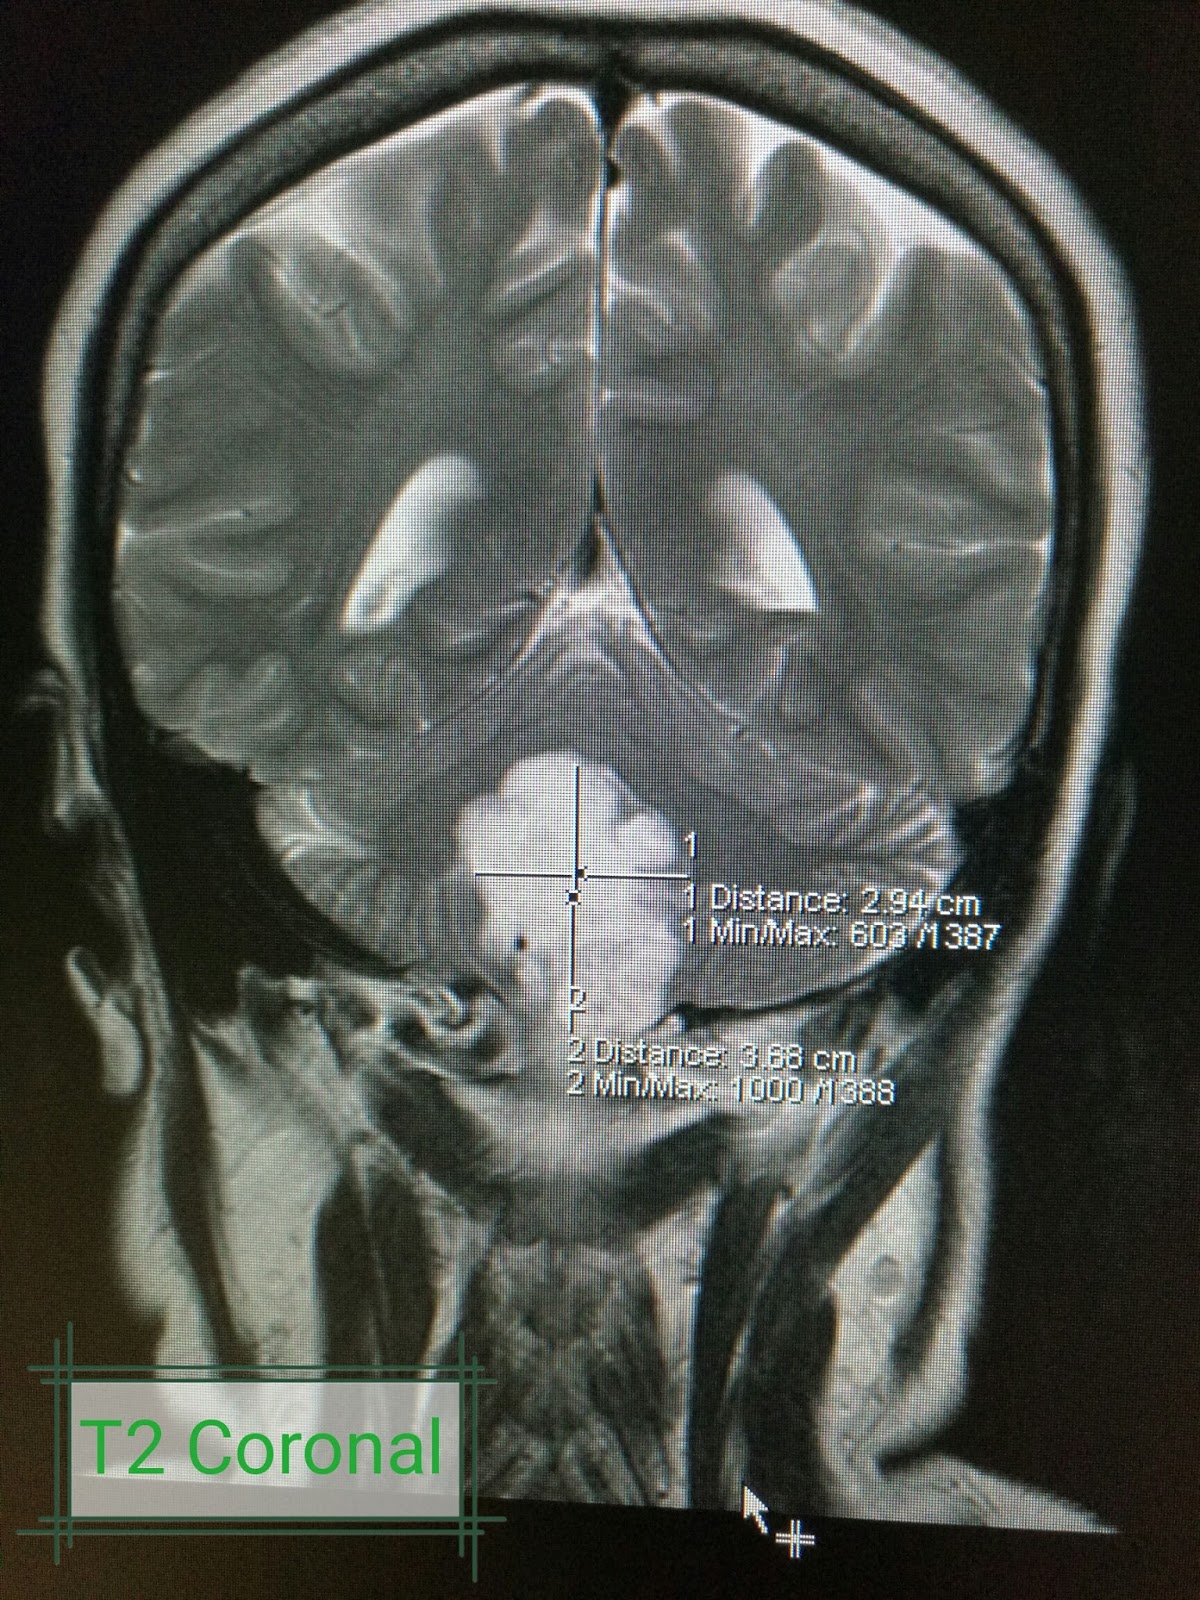

From www.radtechonduty.com

Brain Tumor / Cancer MR Imaging of the Brain RadTechOnDuty Brain Tumor Tight Neck Muscles A brain tumor, especially if it is located in the cerebellum, can cause a stiff neck. However, half of brain tumour patients will experience. Brain tumor symptoms can vary from person to person and depending on where the tumor is in the brain. A seizure or muscle spasms. Brain tumors in the back of the head might cause a headache. Brain Tumor Tight Neck Muscles.